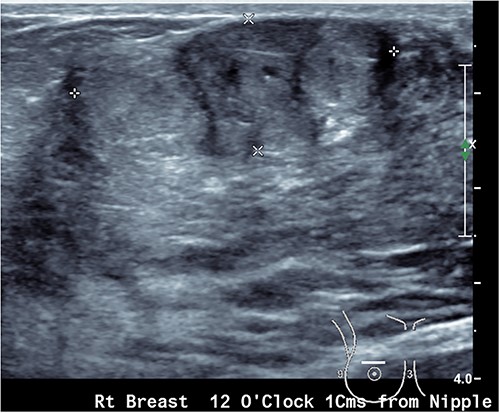

Upon examination, she has B cup breasts. A firm mobile 3 cm lump was palpated at 10 o’clock deep to the areolar edge and there was no palpable axillary lymphadenopathy. The contralateral breast was unremarkable. Ultrasound assessment of the breast demonstrated a lobulated lesion with minimal calcifications measuring 31 × 14 × 19 mm (Figs 1 and 2). No other lesions were detected, and no suspicious lymph nodes were present within the ipsilateral axilla. She proceeded to a core biopsy which demonstrated a fibroepithelial lesion with low cellularity and mitotic figures. A low grade phyllodes tumour could not be excluded based on the core biopsy. Following the discussion of ongoing surveillance, repeat core biopsy or excisional biopsy, the patient decided to proceed with an excision of the lesion.